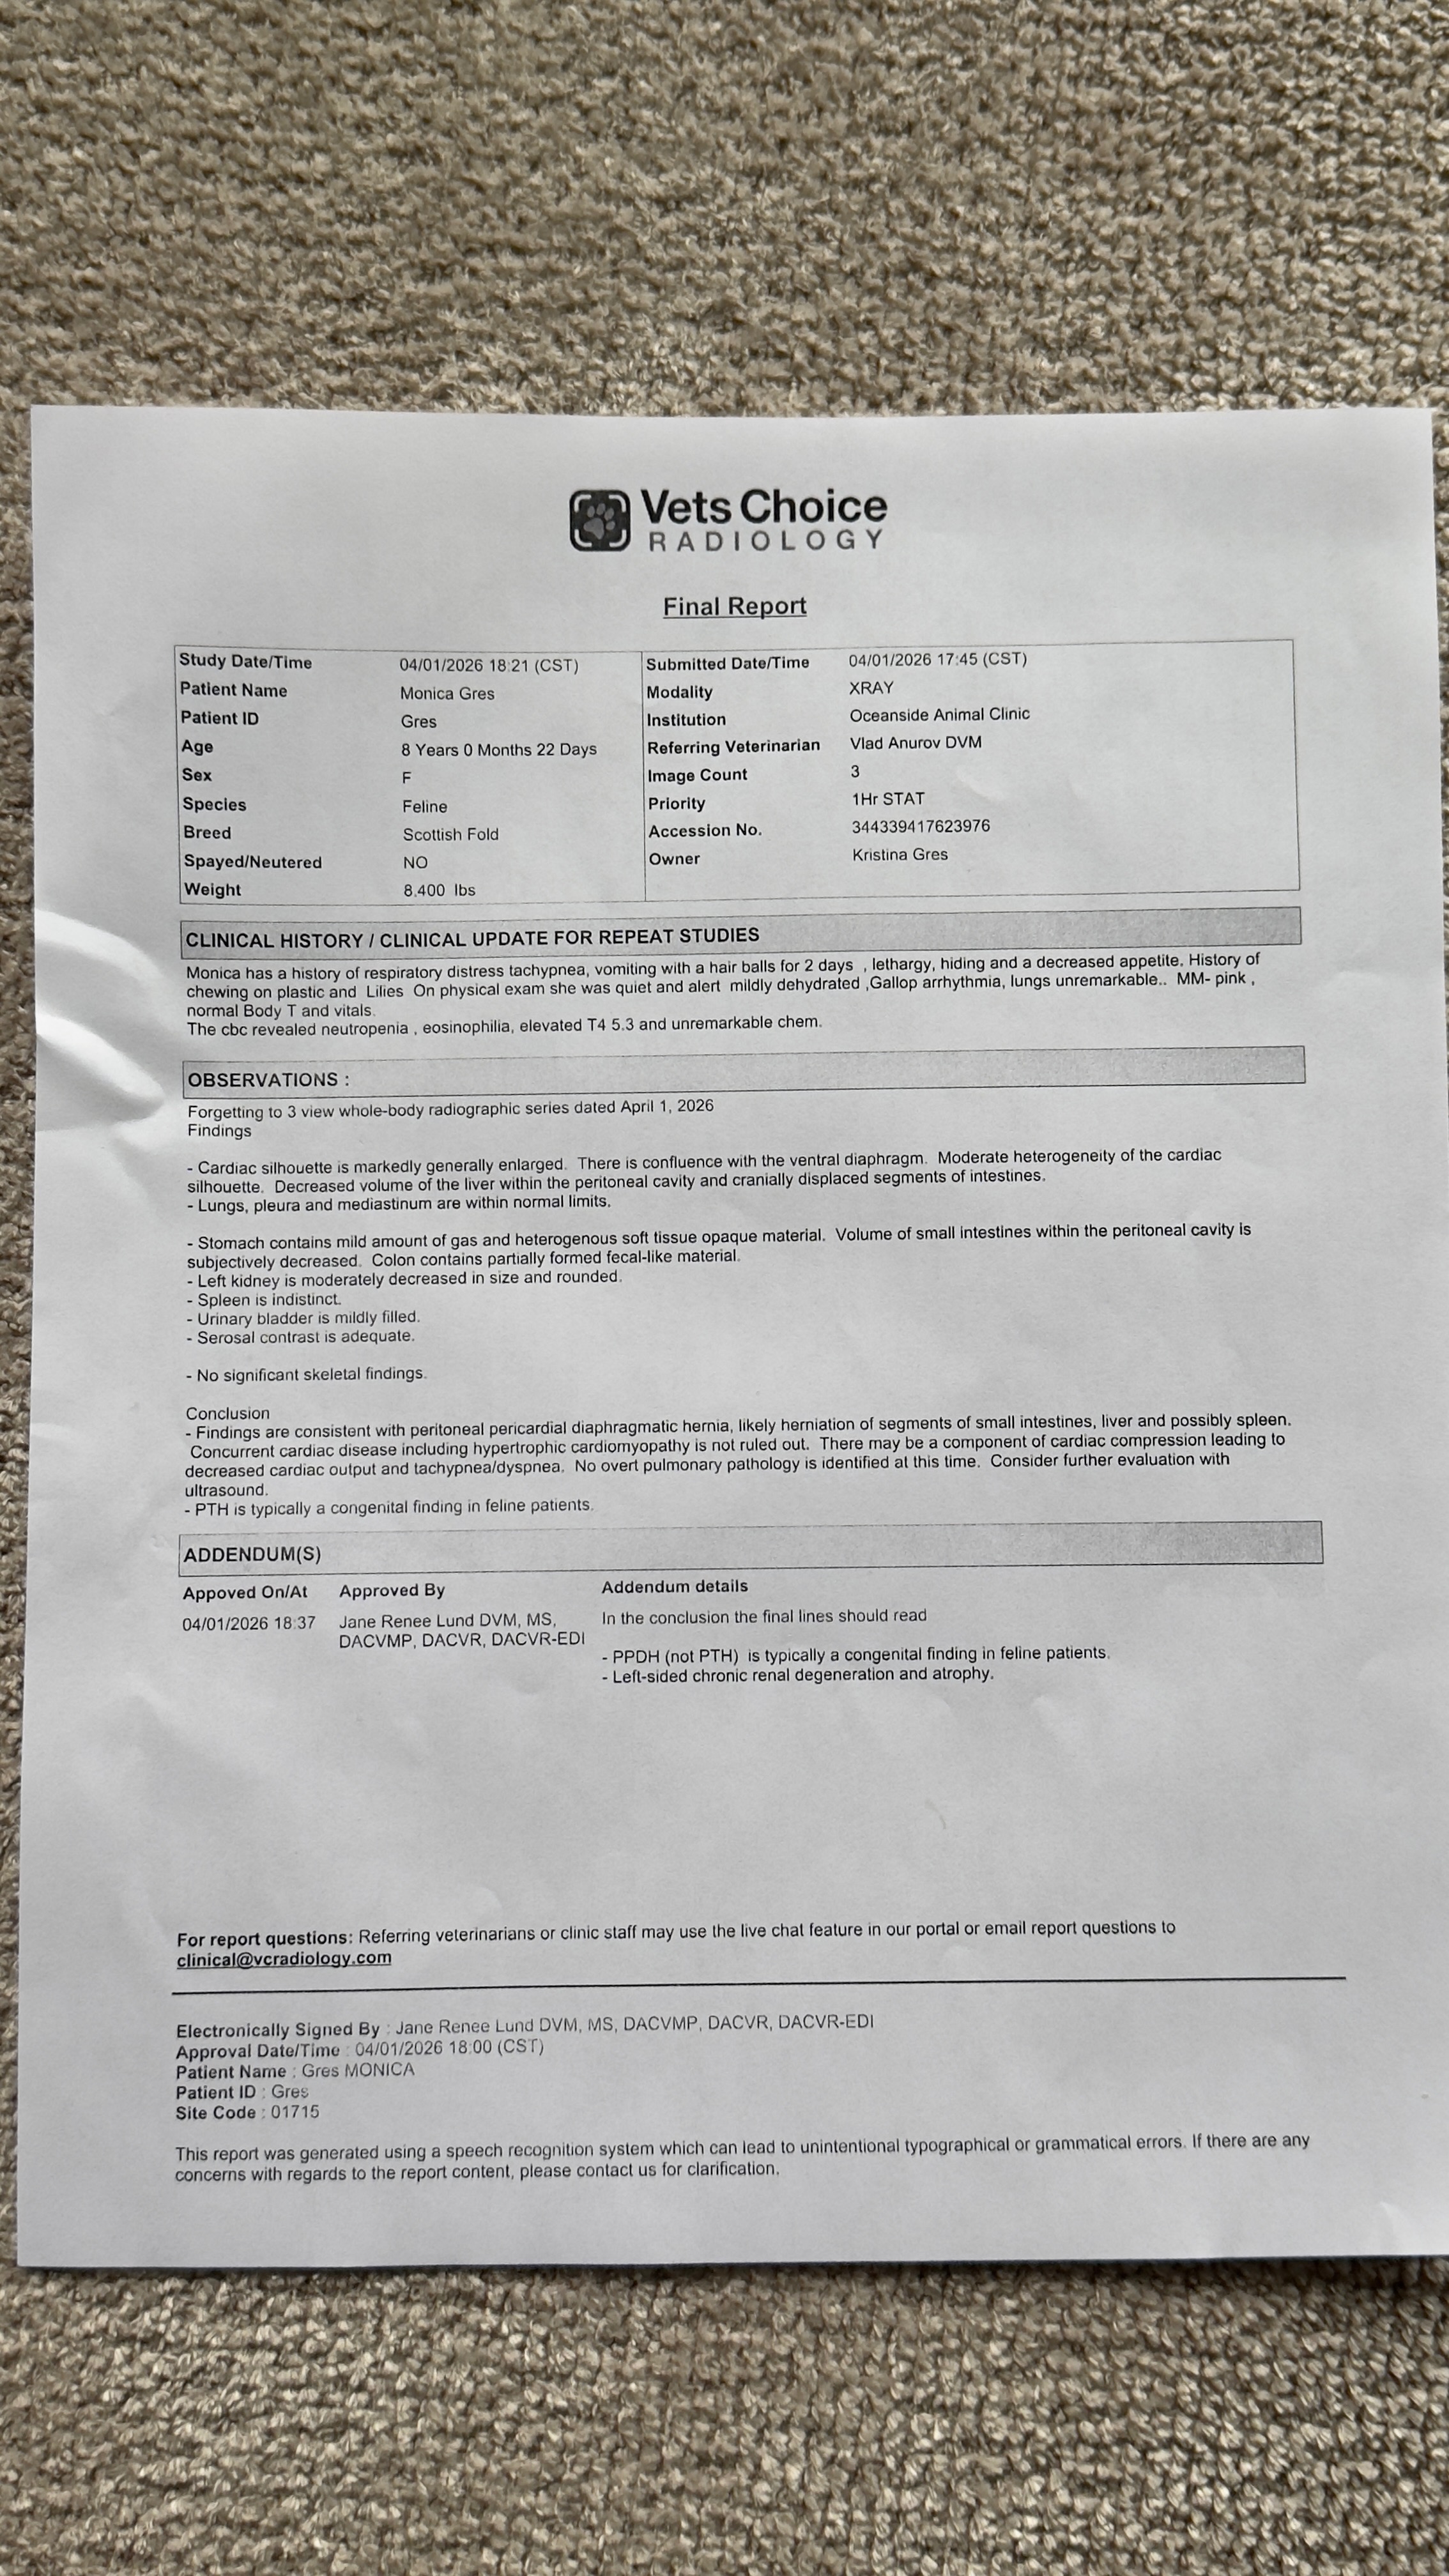

Monica is my 9-year-old cat and my precious sweet angel. She has been with me through the hardest periods of my life, offering comfort when I had no support at all. Now, Monica is facing a critical health crisis. She has a gigantic heart that is pressing on her tissue, a diaphragmic hernia next to it, and possible plastic obstruction in her stomach. Her left kidney is already deformed, causing her discomfort and putting her at high risk. Blood work shows she is intoxicated, and the doctor cannot give her steroids or other medications because of the risks to her heart. Without urgent medical help, her life expectancy is only about three months.

All the funds raised will help me get Monica through the necessary check-ups and treatments, including an echocardiogram, ultrasound, medications, and potential surgery. I have spoken to veterinarians and shared all her results, and they agree that immediate medical intervention is needed to give Monica the best chance. Your support will help cover these costs and ensure Monica receives the care she needs.

All the funds raised will help me get Monica through the necessary check-ups and treatments, including an echocardiogram, ultrasound, medications, and potential surgery. I have spoken to veterinarians and shared all her results, and they agree that immediate medical intervention is needed to give Monica the best chance. Your support will help cover these costs and ensure Monica receives the care she needs.